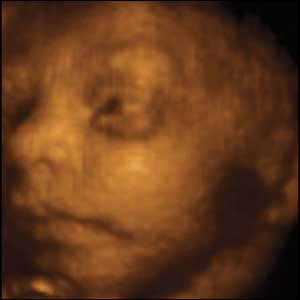

10 weeks gestation, 6cm from crown to rump.

4 of 10

This foetus exhibits behaviour identical to what he will do after birth,. If he's held upright on a flat surface he will try and move forward.